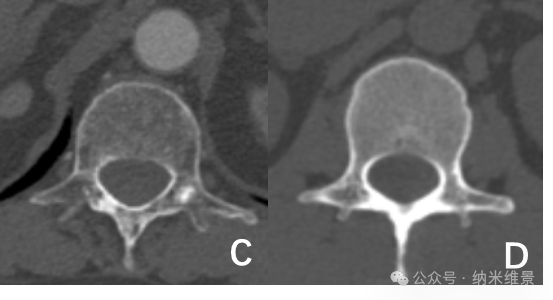

C. 老年骨质疏松患者螺旋CT图 D. 骨量正常的健康志愿者螺旋CT图

苏州大学附属第一医院与纳米维景的联合研究带来突破:相控阵CT凭借"光学旋转"技术,解决了传统CT依赖机械旋转导致的拖尾效应,将空间分辨率大幅提升,能够清晰地观测骨微结构,可精准识别骨质疏松早期的骨小梁改变,显著提高骨折风险预警准确性。

研究团队对100例受试者(老年组33例/中青年组67例)腰椎进行扫描,多项骨微结构指标变化显示:老年骨质疏松患者的骨小梁体积骨密度较中青年组显著下降,骨小梁连接密度有所减少。这种传统CT因分辨率不足难以清晰辨别的区域特异性差异,现可通过相控阵CT清晰呈现。